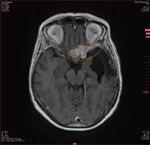

12.11.2024: MRT

• unverändert zur Gamma Knife Behandlungssituation 2021 das kleine links temporale Konvexitätsmeningeom

• Ein progredientes links frontoorbitalis Meningeom (10 mm)

• Ein progredientes Meningeom links frontobasal en-Plaque wachsend mit Raumforderung am linken N.opticus mit Durchmesser 36x13x6mm

• Ein kleines Meningeom links temporamedial am Tentorium (9 mm),

• Ein weiteres sehr kleines links temporales Konvexitätsmeningeom (8 mm),

• Ein progredientes Meningeom links temporaparietaler Übergang (19 x 9 mm)